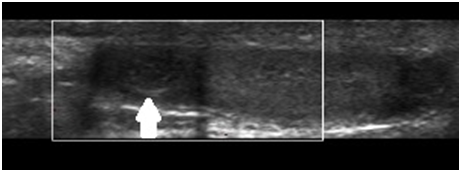

An 8-year-old male patient complaining of pain in the left scrotum for four hours. Relatives deny comorbidities. The patient denies trauma or recent sports. On clinical examination, there is a small blue dot in the painful scrotum. Ultrasound shows preserved testicles, discarding testicular torsion, and a hypoechoic, oval, well-defined image, adjacent to the head of the left epididymis, measuring 6.5 mm, compatible with appendix epididymis torsion (Figure 1). The patient was conducted to conservative treatment – rest and analgesics, with resolution in one week.

Figure 1 Ultrasound shows a preserved left testicle and a hypoechogenic, oval, well-defined image, adjacent to the head of the left epididymis, without vascularization on Doppler study, compatible with torsion of the epididymal appendix (white arrow).